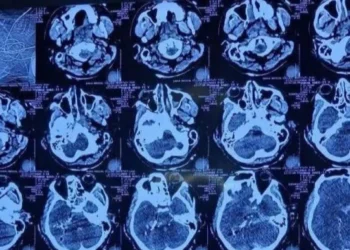

মাথায় গুলিবিদ্ধ ওসমান হাদির মস্তিষ্কের অস্ত্রোপচার সম্পন্ন হয়েছে। তবে তার অবস্থা এখনো সংকটাপন্ন। বর্তমানে তিনি লাইফ সাপোর্টে রয়েছেন। ঢাকা মেডিকেল ...

মাথার একপাশ দিয়ে ঢুকে অন্যপাশ দিয়ে বের হয়ে গেছে গুলি: হাদির চিকিৎসক